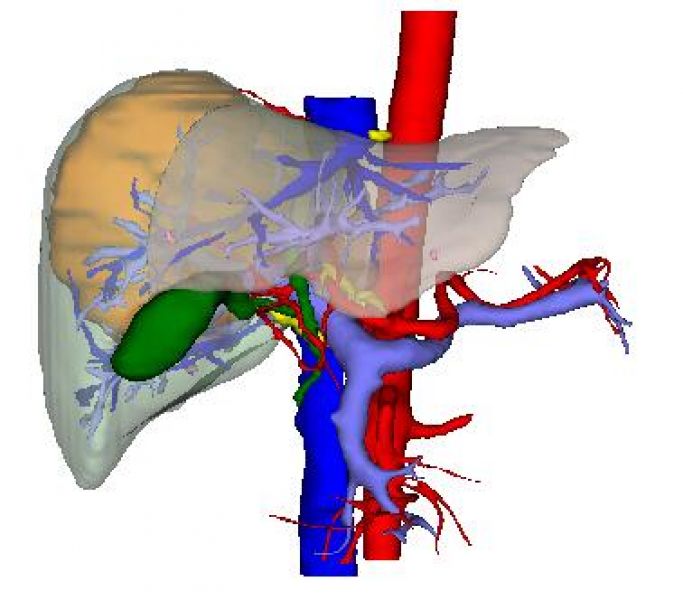

患者入院后肝胆外二科积极诊治,肝胆脾增强CT示:肝右叶占位,性质待定:考虑原发性肝CA(巨块型)并子灶形成,其他待排,AFP〉1210.0ng/ml,乙肝病毒PCR,9.78E+0.4IU/ml。结合病史及相关检查结果,术前诊断:1.右肝占位:原发性肝癌可能性大?2.乙肝。术前请感染科会诊加用恩替卡韦分散片抗病毒治疗。告知患者及家属原发性肝癌可能性大的事实,作为家庭主要劳动力的患者,在病魔面前没有妥协,毅然决定积极配合治疗。面对患者的信任,肝胆外二科治疗团队不敢丝毫懈怠,科主任姚本能主任医师与副主任杨定华副主任医师仔细阅片,经讨论后为患者完善肝脏3D成像,通过3D显像技术,精确了解瘤体位置和瘤体与动、静脉关系。术前精准评估,明确肝肿瘤主要位于肝S7、少部分位于肝S5、S8。因瘤体巨大,位置深,合并乙肝肝硬化,术中显露困难,手术难度极大。又组织全科室医师术前讨论,为了减少术中对肿瘤的挤压,拟定了行胸腹联合切口实施手术的方式,实现肝癌根治性切除,使患者最大程度获益。

术前3D成像图片